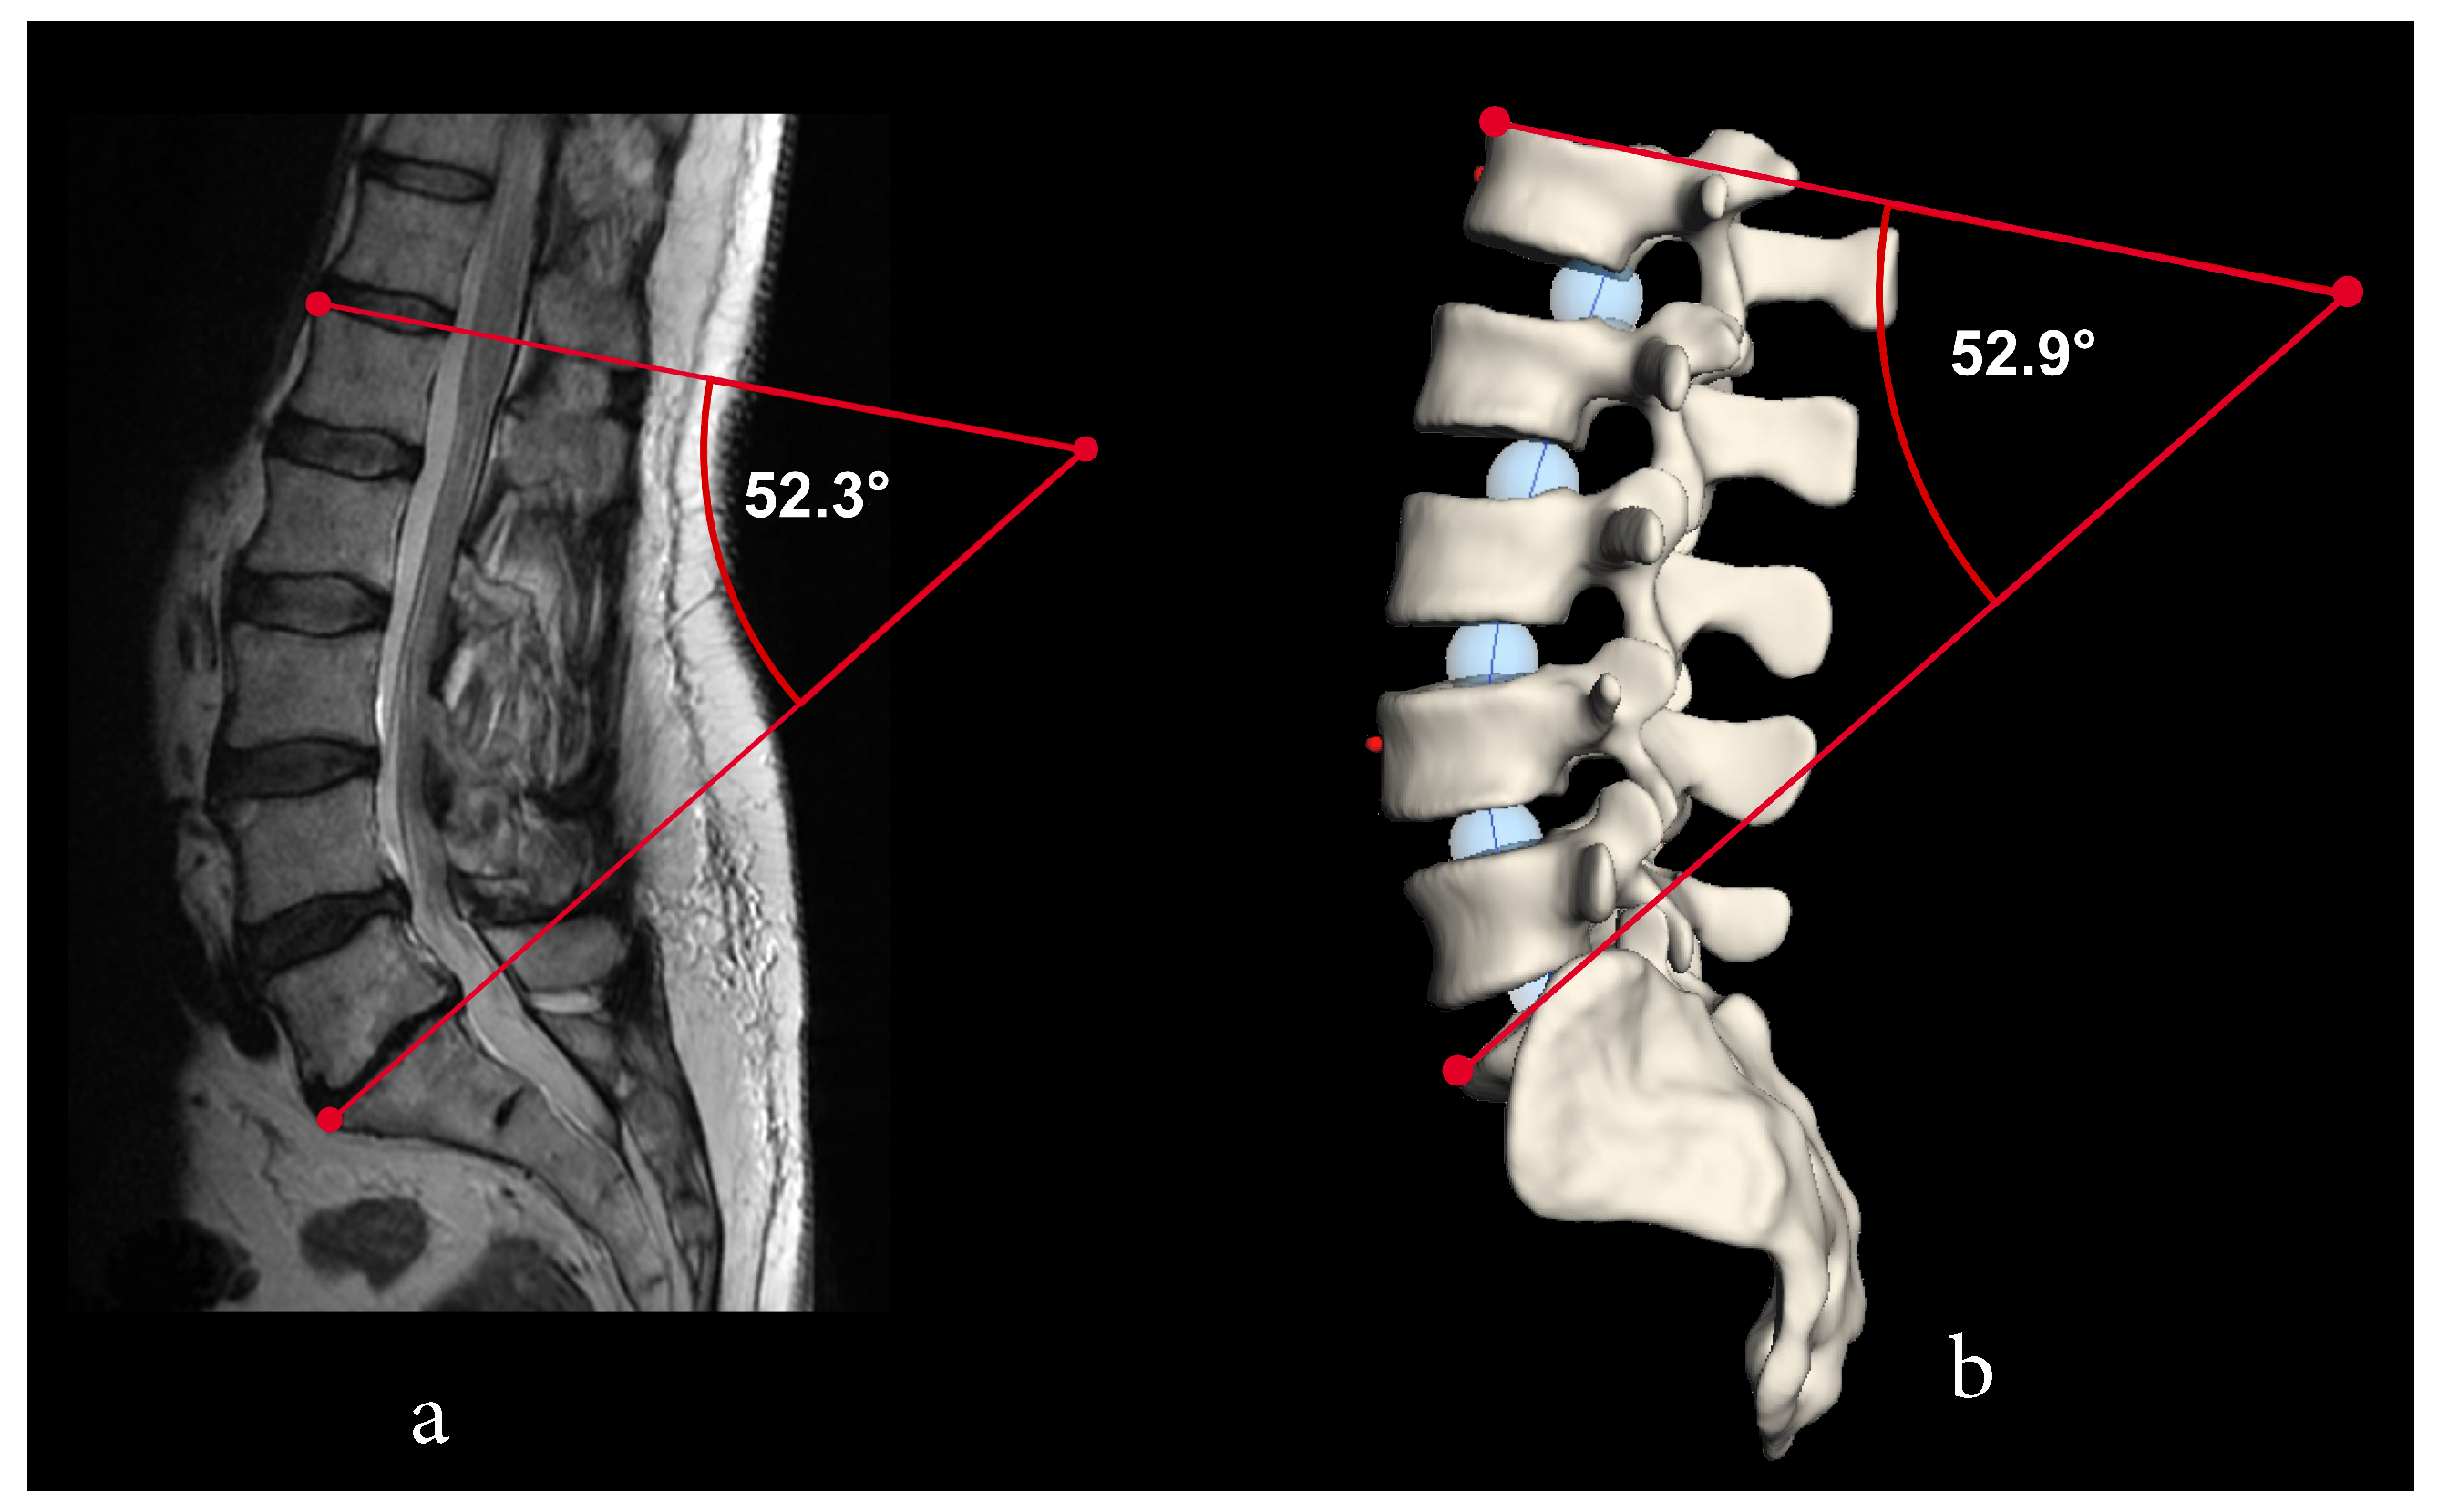

3. Results

3.2. Creation of New Lordosis Model from 3D Curvature

| Test Person | Rater 1 [] | Rater 2 [] | Rater 3 [] | Mean [] | SD [] |

|---|---|---|---|---|---|

| 33.8 | 33.8 | 33.7 | 33.8 | 0.057 | |

| 34.0 | 33.5 | 34.5 | 34.0 | 0.5 | |

| 45.5 | 45.4 | 45.3 | 45.4 | 0.1 | |

| 47.5 | 46.4 | 47.2 | 47.0 | 0.6 | |

| 52.3 | 52.8 | 57.1 | 54.1 | 2.6 | |

| 52.9 | 52.8 | 52.7 | 52.8 | 0.3 |